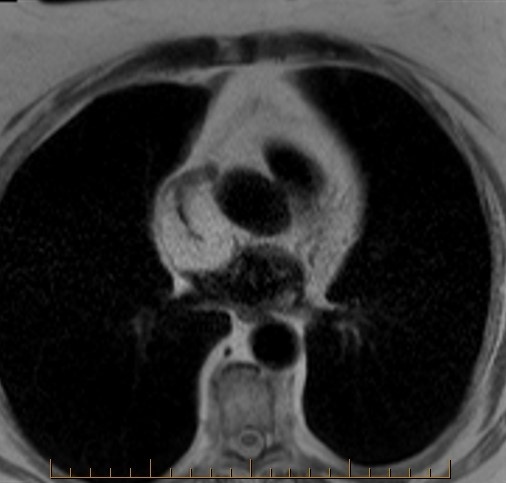

Where is the squeeze play here on axial T1 cardiac MRI?

The squeeze play here is a fatty tumor compressing the superior vena cava. The vena cava is normally round. Here, it appears squeezed or slit-like (second image, arrow). This could lead to superior vena cava syndrome. Surveillance recommended every 6 months. The third MR image shows signs of right ventricular dysplasia. The anterior right ventricle is lobulated, irregular and exhibits sparse fat signal.